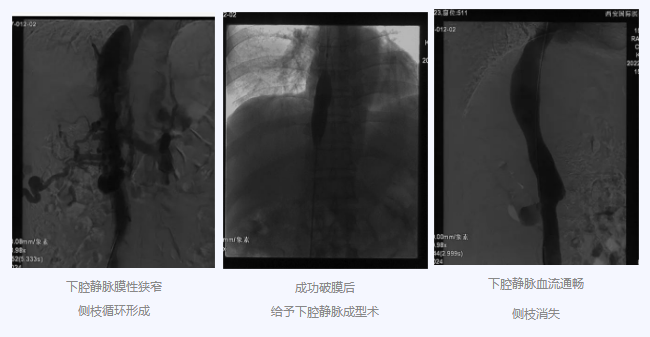

入院后,在韓國(guó)宏院長(zhǎng)的安排下,臨床經(jīng)驗(yàn)豐富的醫(yī)師給老謝做了B超、CT 等檢查,結(jié)果顯示:三支肝靜脈近心端閉塞,肝內(nèi)側(cè)枝循環(huán)形成,下腔靜脈近心房入口處隔膜樣狹窄,隨后的DSA血管造影也證實(shí):下腔靜脈狹窄,且有側(cè)枝形成,最終確診困擾老謝20年的疾病為混合型布加綜合征,是一種罕見(jiàn)病。

明確診斷后,韓院長(zhǎng)帶領(lǐng)團(tuán)隊(duì)縝密分析老謝的病情,為其制定最佳的治療方案,考慮到老謝的根本病因是下腔靜脈阻塞,介入手術(shù)成為首選治療方法,通過(guò)微創(chuàng)介入手術(shù),可準(zhǔn)確打通患者的閉塞血管,癥狀迅速緩解。做好充分術(shù)前準(zhǔn)備后,為患者行“下腔靜脈成型術(shù)”,精準(zhǔn)定位快速貫通,閉塞的下腔靜脈順利開(kāi)通,手術(shù)圓滿完成。